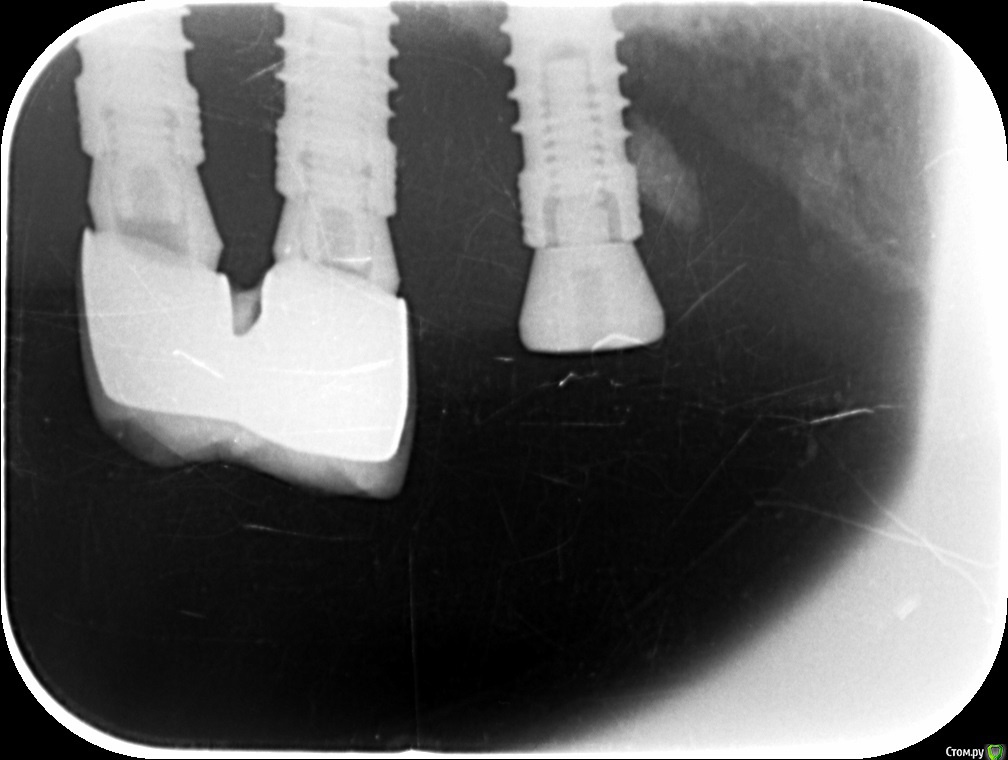

doktorSergey Опубликовано 25 января, 2018 Поделиться Опубликовано 25 января, 2018 Уважаемые коллеги, не откажите в просьбе. Имеет не конусное внутреннее соединение, и восьмигранный позиционер.Ума не приложу, кто это. Ссылка на комментарий